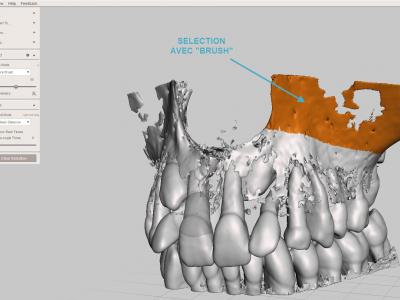

Sélectionner la surface de zone à éliminer avec l'outil "Select" "Brush", puis les supprimer avec le raccourci clavier "X"